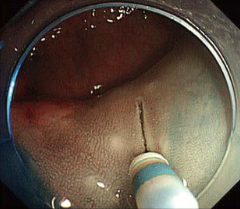

粘膜下層へのナイフ送液が可能に新たに送液機能を付加したことで、切開後、デバイス交換なしにナイフのまま露出した粘膜下層への送液が実現します。

吸引能を維持しながら

スムーズな操作をサポート外径2.0mmの細いシースの採用により、鉗子チャンネル内に挿入した状態でも、スコープ吸引能は従来品と同等。

さらに適度にコシのあるシースにより操作がしやすく、線維化した組織でもスムーズな切開・剥離をサポートします。 -